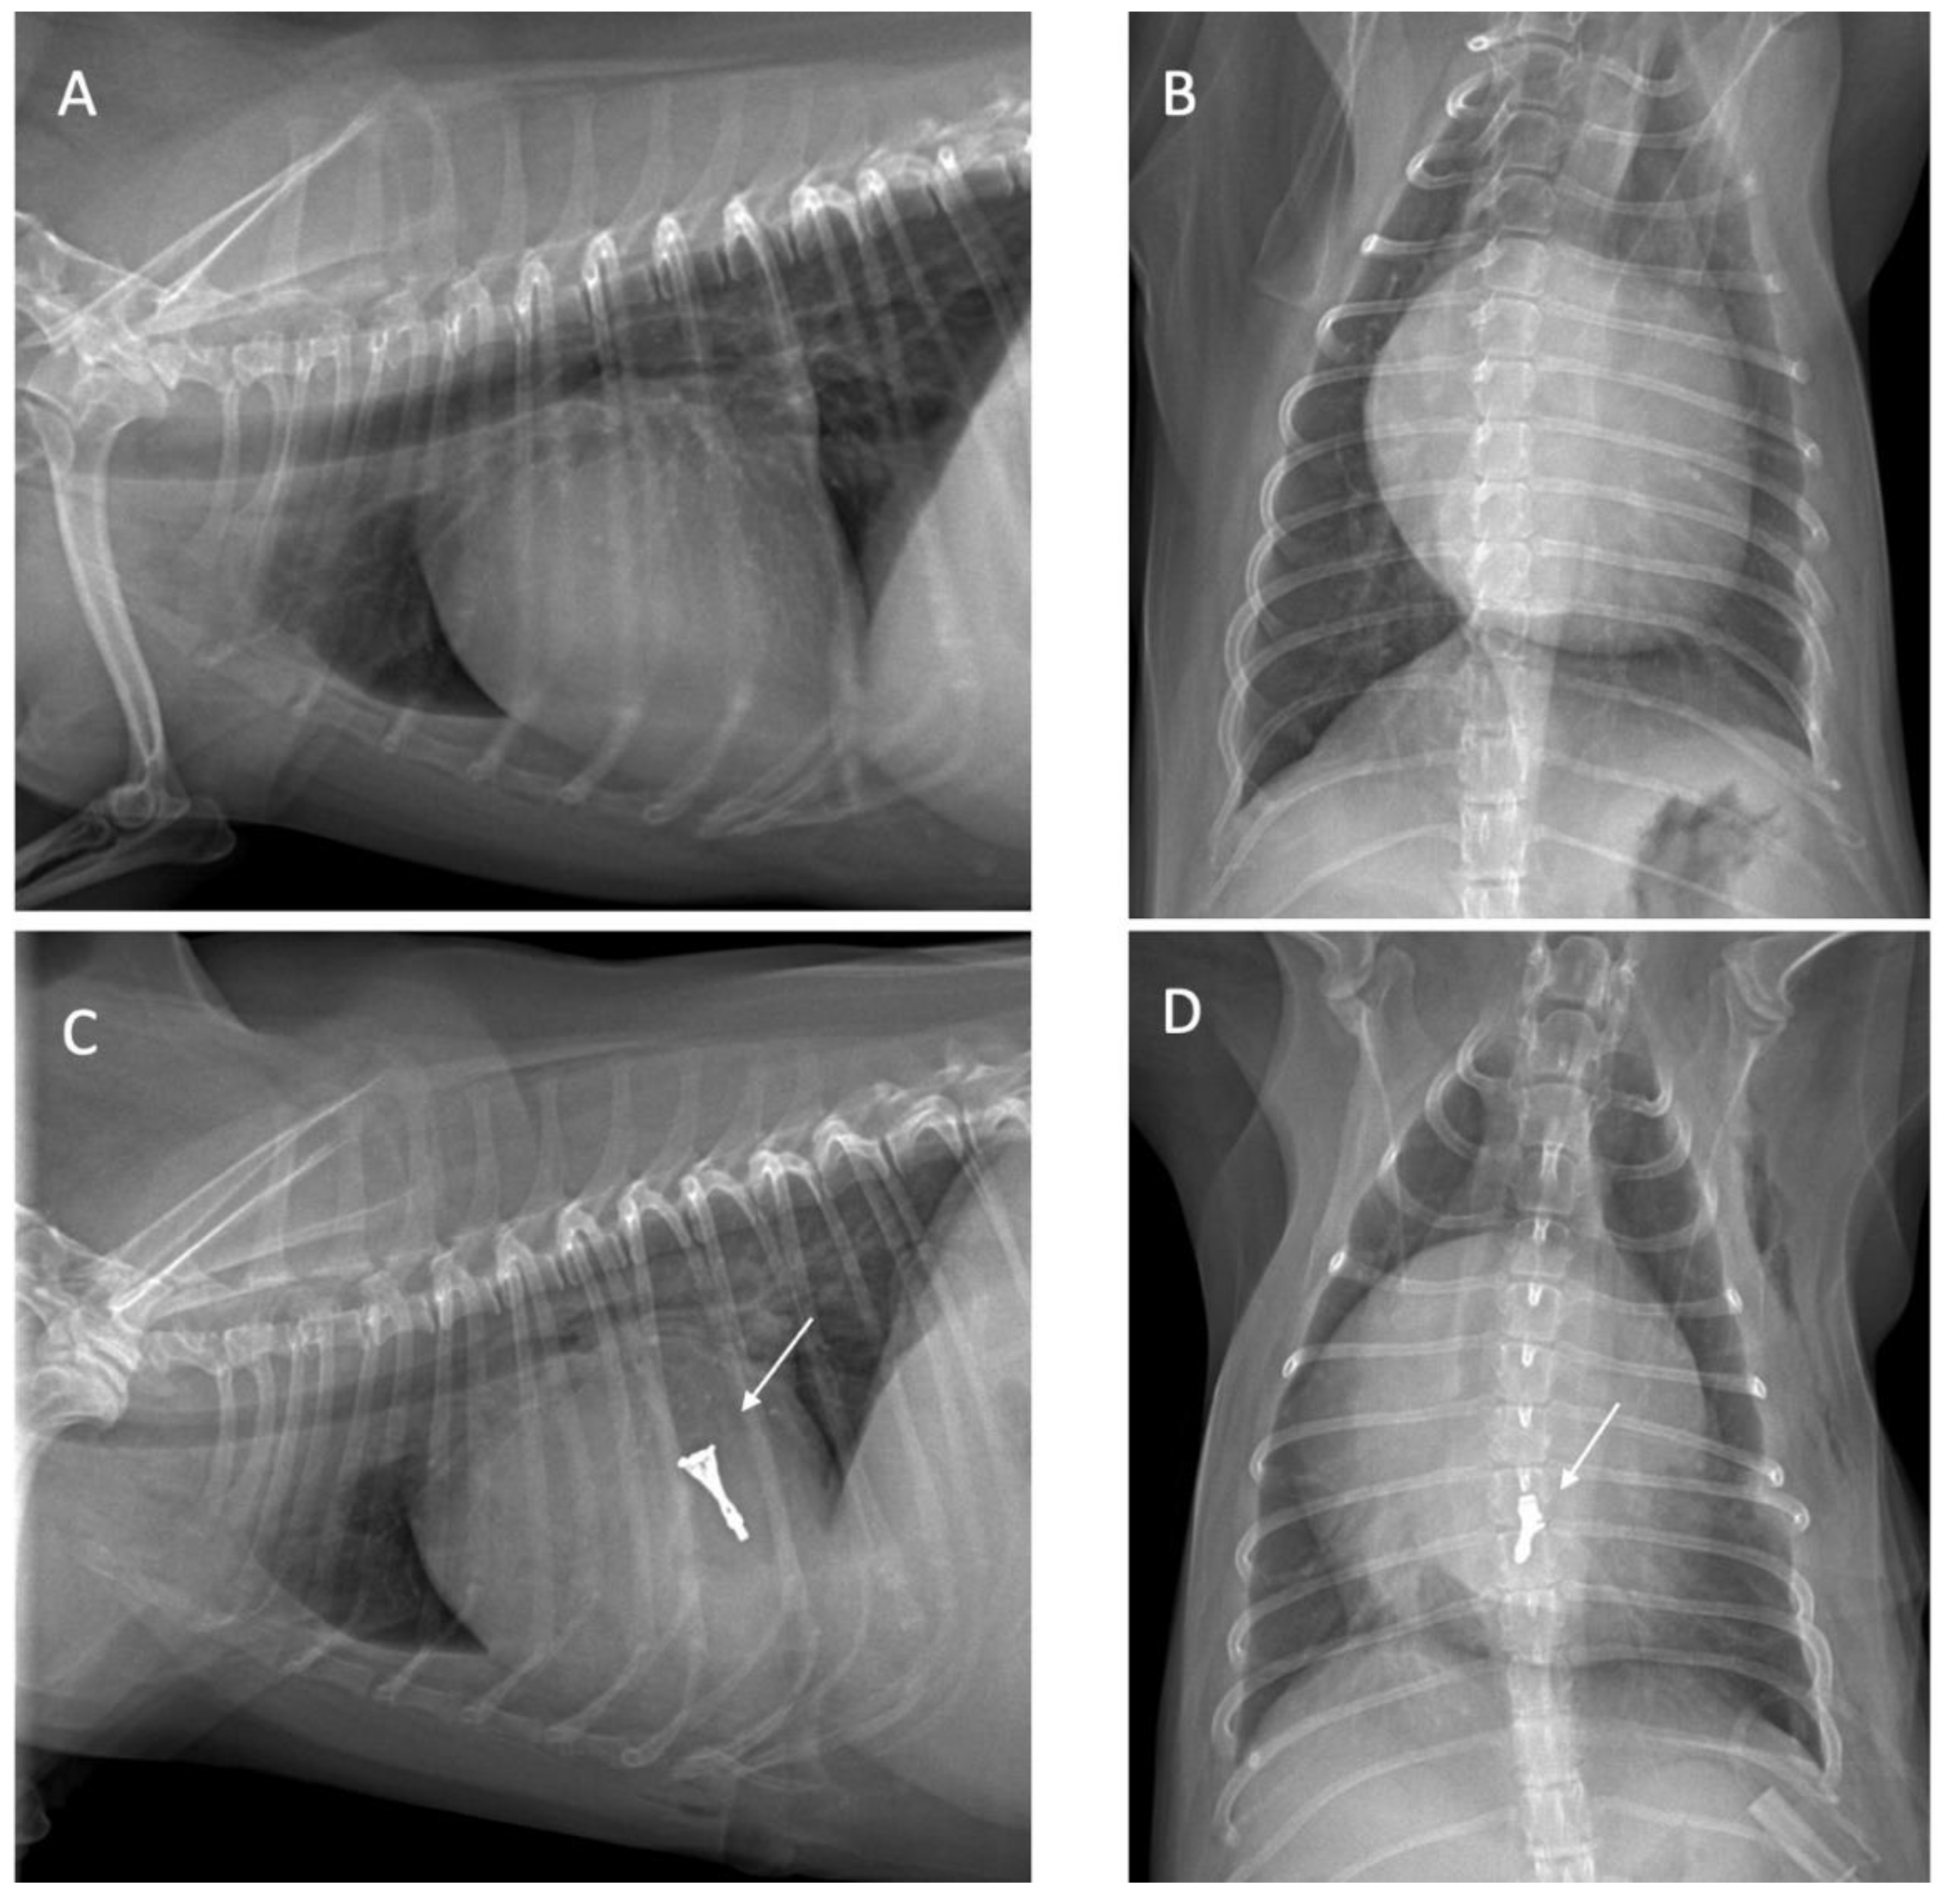

All dogs were assessed for a physical examination (inspection, palpation, percussion, and auscultation), for general health status. In this evaluation, mucous membranes, capillary refill time, rectal temperature, heart rate, heart sounds, pulse rate, and state of hydration were assessed. The dogs presented with a history of coughing, dyspnea, and exercise intolerance. Thoracic radiography revealed left heart enlargement (Figure 1). The mitral valve structure was evaluated by 3D transesophageal echocardiography, and a satisfactory clamp position was confirmed using fluoroscopy and 3D- TEE as shown in Figure 2 and Figure 3.

Surgical intervention

Surgical intervention was performed using a v-clamp device in 4 patients as shown in Table 2. The surgical procedure has been described previously [14,15]. In brief, an incision was made at the left 5th intercostal space. A 2-0 polypropylene monofilament purse-string suture was placed at the puncture area and then a 14 French sheath introducer (HongYu Medical Technology, Shanghai, China.) was guided into the left ventricle, and the v-clamp device was inserted through the sheath and positioned in the left ventricle under transesophageal echocardiography and 3D imaging (Figure 2). Limb-lead electrocardiography was used to determine the cardiac rhythm. The mitral valve leaflet was repaired by v-clamp. After the mitral valve was clipped, the guiding catheter was removed and flushed, and then the skin was sutured with a surgical nylon. A chest drainage tube and a urinary catheter were placed after completing the surgical procedure. Chest drainage is used for the removal of air, fluid, or blood. Postoperative urine monitoring is also important for identifying any post-operative complications. Patients were recovered in a cage filled with oxygen for 24-48 hours. For 24 hours after surgery, the chest drainage and the urinary catheter were removed. The blood profiles and thoracic radiographs were evaluated every day until discharge.

Figure 3. A V-clamp device placement (black arrow) with an introducer sheath of 14 millimeters was inserted into the left atrium. A satisfactory clamp position was confirmed using fluoroscopy guidance.